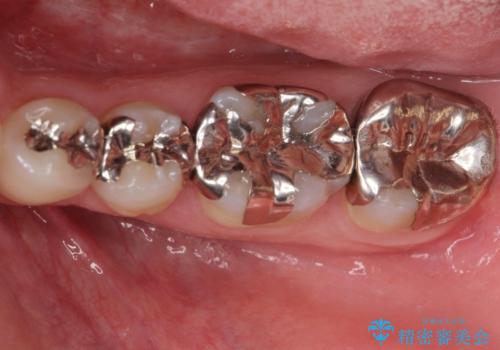

- 銀歯を白くしたくて来院。

銀歯を外して被せ物の予定でしたが歯の高さが低く取れやすい被せ物になってしまうため歯の高さを変える手術を行いました。

まずはメタルを全て外し仮歯にして、手前のメタルインレーは手術前にセラミックインレーの治療を行いました。